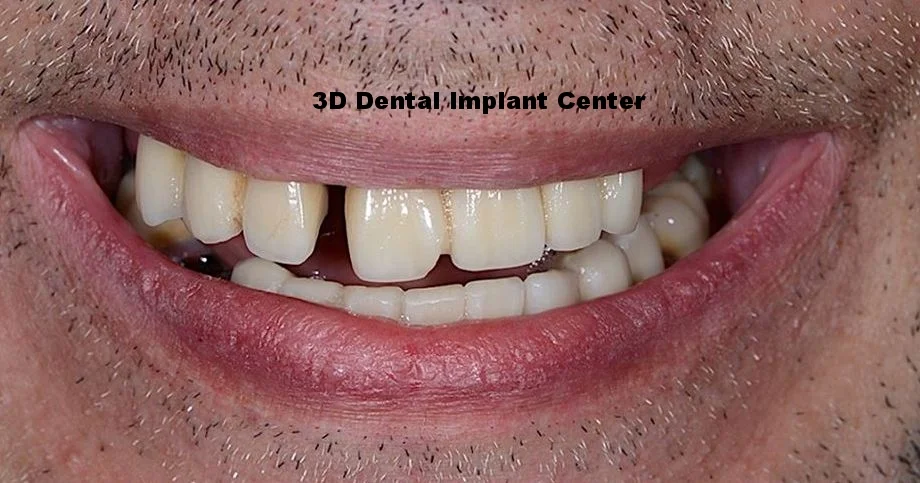

Case #2: Patient presents with teeth that kept giving him pain despite undergoing years of root canal treatments and gum disease treatments. We discussed treatment options and planned for upper and lower all on 8. All his upper teeth were extracted, bone grafted, dental implant placed on the first day, and did the same thing on his lower teeth few days later. Final prosthesis was delivered 6 months later. Patient is very happy with the result.

Before - patient have very loose bridge and cannot eat. Patient also have severe gag reflex and CANNOT tolearte removable full dentures.

Before - Patient suffers from full mouth decay and broken down dentition.